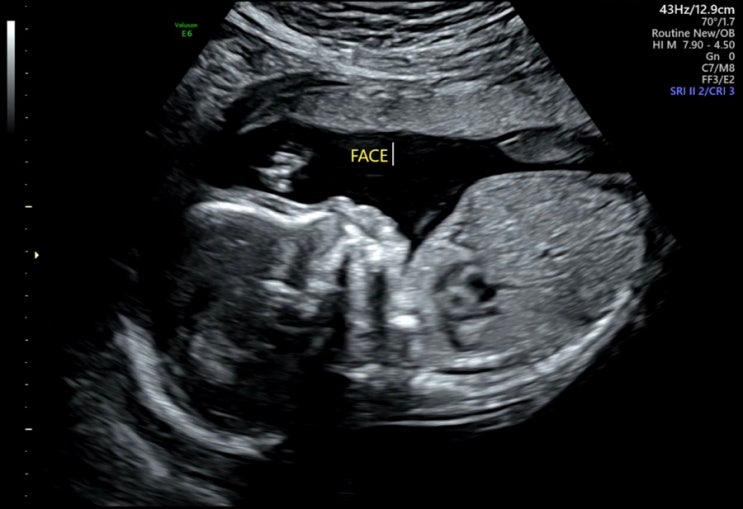

임신 20주차) 정밀초음파 / 임산부 몸무게 / 임산부 엽떡 / 노시부 수유나시 리안드림콧 핫딜

임신 20주 기록 임신 20주차이자, 6개월차 진입! 먹부림 20대 초까지는 단 음료를 좋아했었지만 30대가 되...